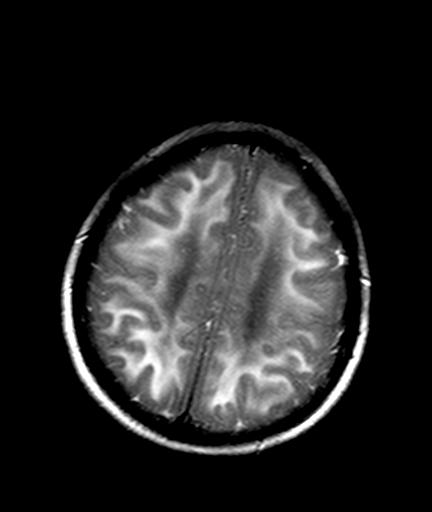

发热、头痛伴精神异常1周

较对称性脑白质异常信号,深部白质t2明显低信号(铁质沉积过多?)

考虑脑白质病变,请结合临床病史及实验室检查进一步分析。

f 23岁